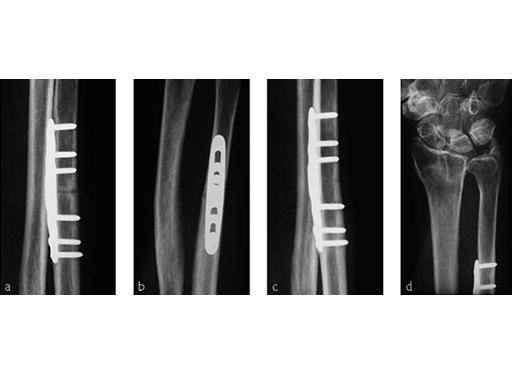

A 69-year-old female patient had suffered a right distal radius fracture one year earlier, and received conservative management. Symptoms included pain and impaired function about the wrist and forearm, with decreased forearm rotation. Painful DRUJ (DASH: 34, PWRE: 29).